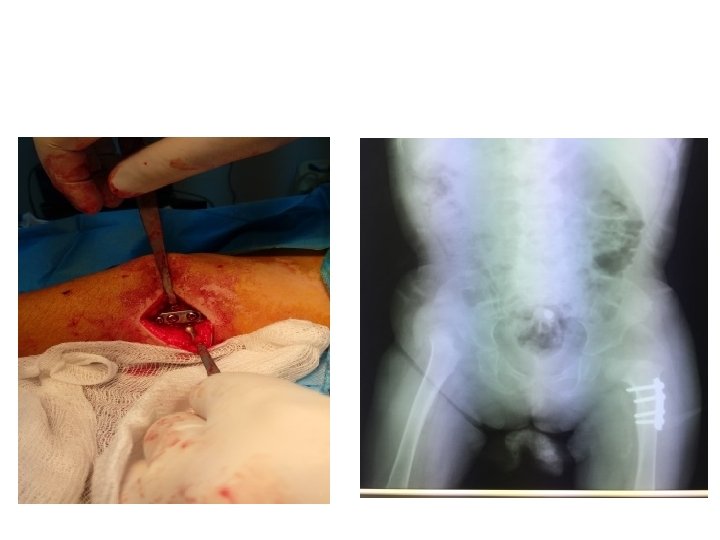

Somerville technique of anterior open reduction in congenital dislocation of hip. A, Bikini incision.

Somerville technique of anterior open reduction in congenital dislocation of hip. A, Bikini incision. B, Division of sartorius and rectus femoris tendons and iliac epiphysis. C, T-shaped incision of capsule. D, Capsulotomy of hip and use of ligamentum teres to find true acetabulum. E, Radial incisions in acetabular labrum and removal of all pulvinar from depth of true acetabulum. F, Reduction and capsulorrhaphy after excision of redundant capsule. G, Developmental dislocation of right hip. H, After anterolateral open reduction. I, At age 7 years; note remodeling of femoral head and acetabulum.